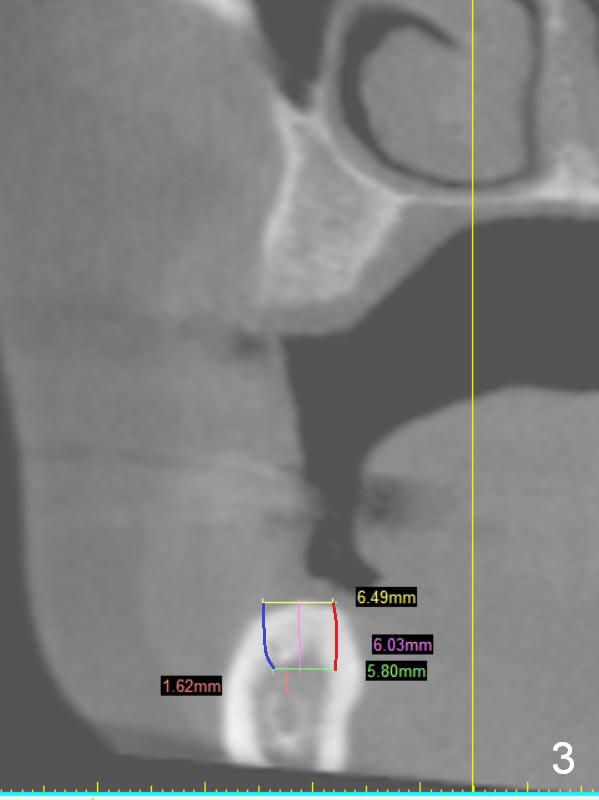

A 49-year-old lady is petit.  The crest at #30 is narrow.  A small implant is placed.  To increase its longevity, the patient should have left 1st molar occlusion.   Bone density at #19 is D1 (the cortex), D4 (upper medulla) and D3 (lower medulla) (Fig.1).  Bone is wide enough to hold a 6 mm (in diameter) implant, but a 8 mm long implant appears to be too long (Fig.2).  Therefore, a 6 or 6.5x6 mm implant appears to be appropriate (Fig.3).  How about the bone at #14?